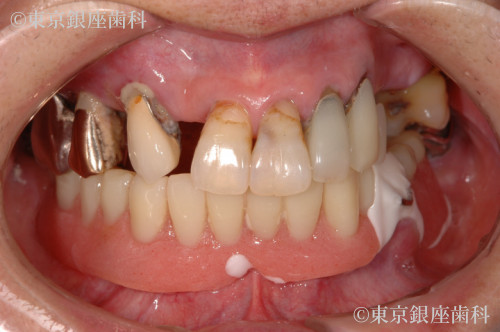

20年経過したインプラントの上部構造を再度新製し快適性を取り戻した80歳代女性の症例

Before

20年前にワンデイインプラントを実施。土台は安定していたが人工歯が経年劣化し再度新製を選択。スペアも作成し将来の負担を軽減した。